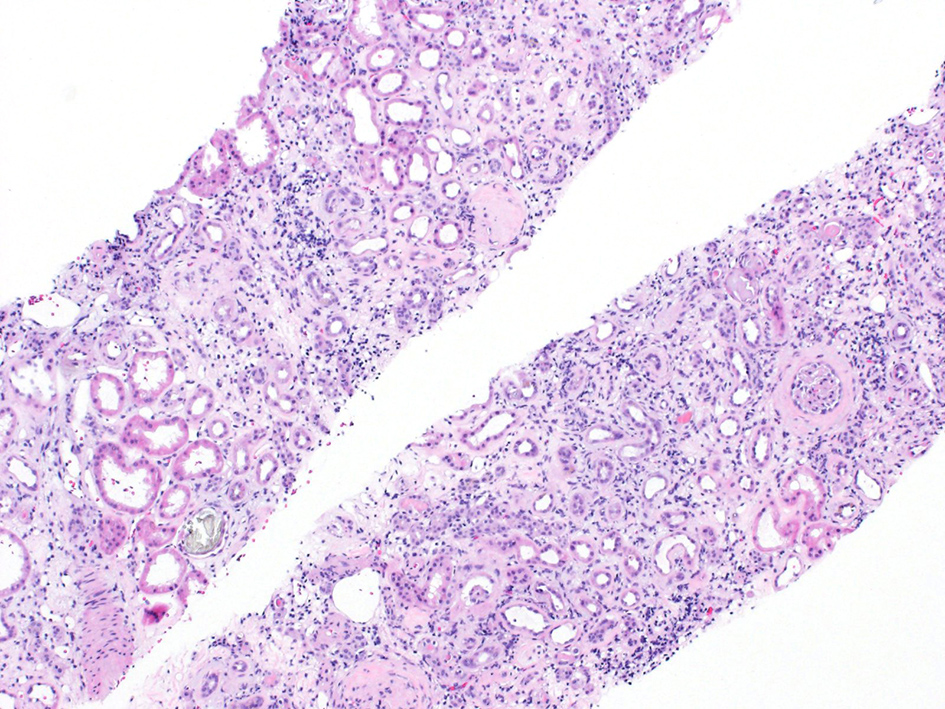

After several days of care and an unremarkable renal ultrasound, a renal biopsy was ordered. The pathology demonstrated 13 out of 23 glomeruli to be globally sclerotic, as well as areas of capillary loop wrinkling and periglomerular fibrosis (Fig. 1). Patchy areas of acute tubular injury were present, with moderate numbers of injured tubules containing luminal calcium oxalate crystals, consistent with oxalate nephropathy (Figs. 2 and 3). Additionally, there was severe interstitial fibrosis and tubular atrophy involving an estimated 60% of the submitted parenchyma, and moderate fibrointimal thickening of small arteries and severe hyalinosis of arterioles (Fig. 4). Immunofluorescence staining for IgG, IgM, IgA, C3, C1q, albumin and fibrinogen were negative, and kappa and lambda light chains stained equally throughout the tubulointerstitium.

![]() Click for large image | Figure 4. H&E stain showing interstitial fibrosis and inflammation. H&E: hematoxylin and eosin. |